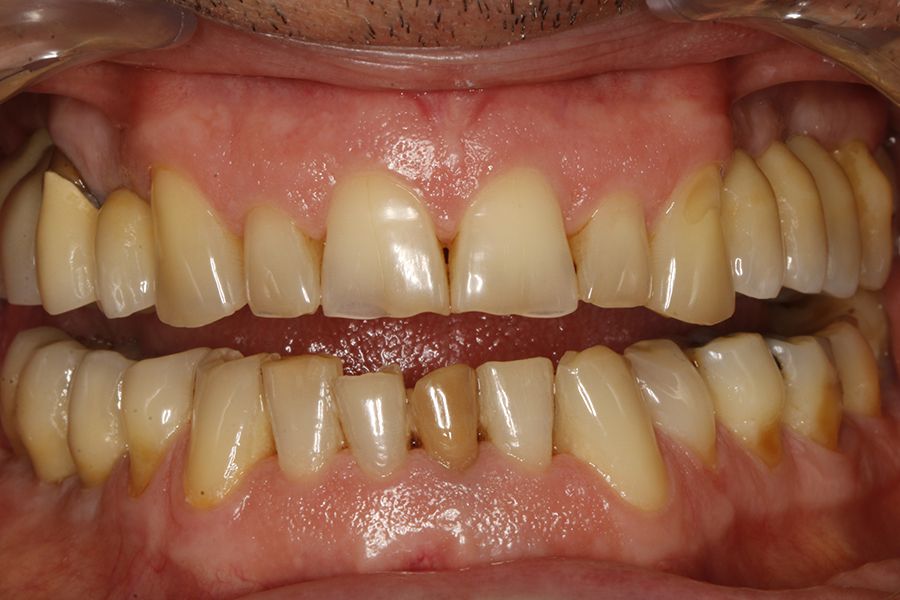

sleep disorders such as OSA and oral pathology, for example bruxism or fractures, of various rehabilitations, both on teeth and on implants, is widely documented today. This association has been demonstrated in several epidemiological studies over the years3-7, with our research group highlighting that the presence of dental wear in patients should prompt a thorough sleep analysis, as the degree of dental wear is directly related to OSA via the AHI (apnoea-hypopnoea index)9-11. This relationship is directly proportional, and it is confirmed that patients with more severe wear also exhibit a higher AHI, which is likewise associated with an increased incidence of fractures in enamel, dental roots, and prostheses. Mechanical events may,

in some cases, also affect implants, resulting in bone defects due to overload, and in extreme cases, leading to fracture of the implant itself.12-14. In the following clinical case series, we sought to retrospectively collect a group of patients who experienced adverse events in implant-supported prostheses associated with mechanical overload (fractures, loosening), to whom a subsequent polygraphic sleep study was performed, identifying those in whom these events could be related to the presence of OSA. The most severe cases identified (AHI ≥ 20) were analysed to obtain data correlating both events (OSA and mechanical complications).